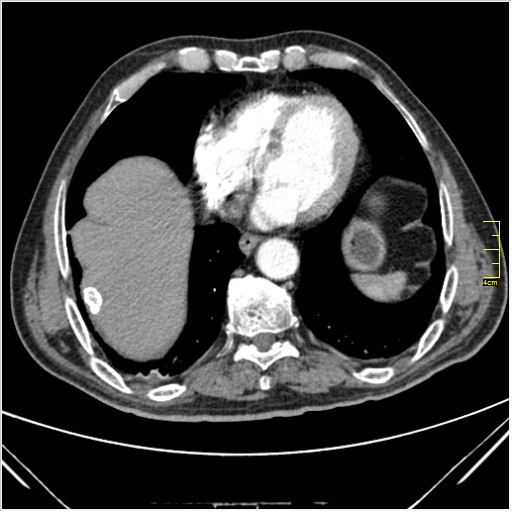

Мужчина 62 года с желтухой

Опухоль головки поджелудочной железы, расширение холедоха и панкреат. протока (Double Channel sign)

Карциномы панкреас гиподенсны на КТ с болюсом, т.к. содержать много соединительной и фиброзной ткани, в отличие от нормальной ткани железы, которая (как любая железа) хорошо васкуляризирована. Поэтому если видим в панкреас солидное гиподенсное образование - всегда настораживает на предмет рака. Второй момент: обязательная оценка взаимоотношения опухоли к ВБА и ВБВ, на предмет оценки операбельности.